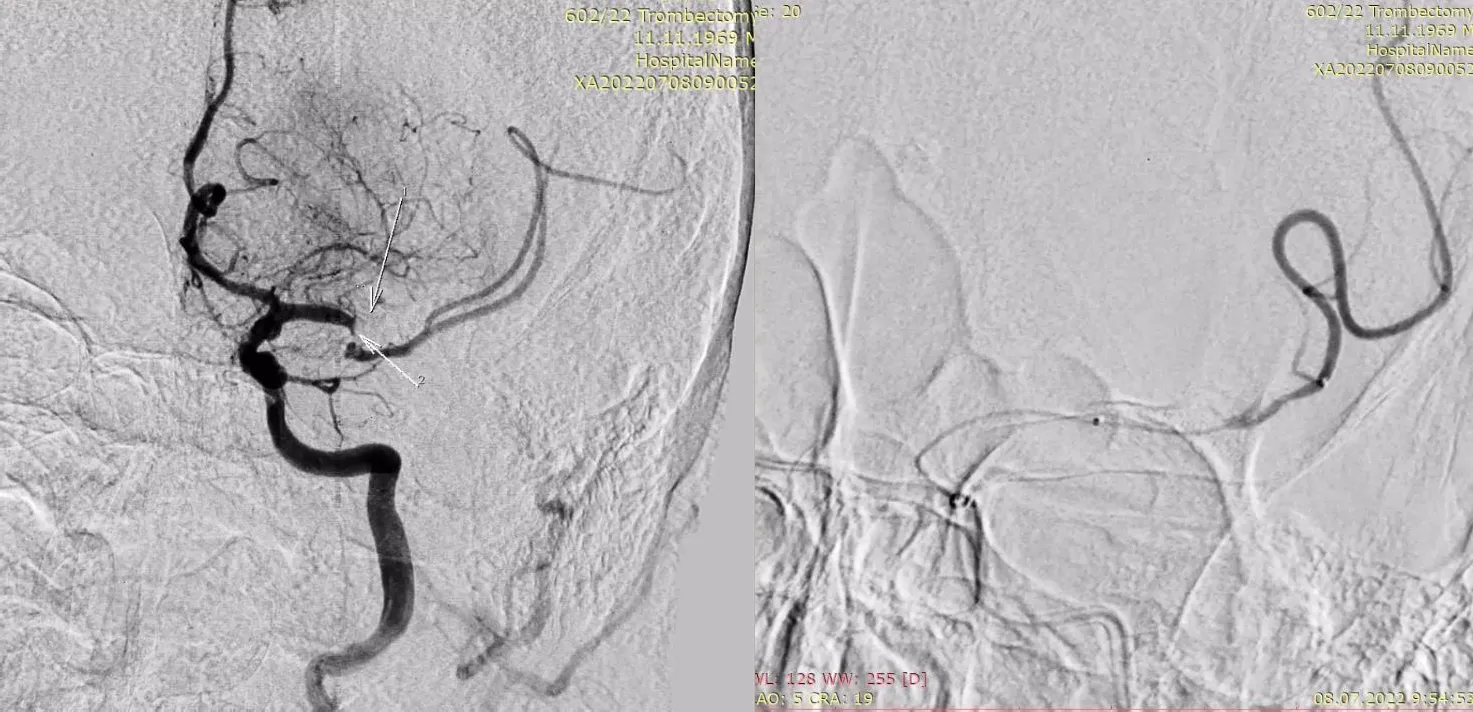

Для анестезіологічного забезпечення механічної тромбектомії застосовували седацію зі збереженням свідомості із забезпеченням кисневої підтримки через маску – 4 л/хв. АТ при ініціальному вимірюванні дорівнював 183/95 мм рт.ст. та не знижувався до моменту реперфузії басейну СМА. Час від початку захворювання до пункції стегнової артерії в ендоваскулярній операційній – 1255 хвилин. Оскільки дані МСКТ – ангіографії вказували на тандемну оклюзію (устя лівої ВСА та сегменту М1 лівої СМА) та демонстрували хорошу колатеральну компенсацію басейну лівої СМА, трансфеморальним доступом операційним провідниковим катетером відразу була проведена катетеризація лівої загальної сонної артерії без етапу діагностичної ангіографії. Цифрова субтракційна ангіографія дозволила з’ясувати місце відходження лівої ВСА від загальної сонної артерії та за допомогою балонного катетера для черезшкірної ангіопластики (percutaneous transluminal angioplasty balloon catheter) сформувати канал на рівні тромбованої атеросклеротичної бляшки ВСА (рис. 4) з метою проведення за межі оклюзії у дистальному напрямку операційного провідникового катетера.

Рисунок 4. Цифрова субтракційна ангіографія, лівий каротидний басейн, ліва косо- фронтальна проекція. Місце відходження лівої ВСА від загальної сонної артерії (червона стрілка). Наповнення балонного катетера на рівні тромбованої атеросклеротичної бляшки (балон позначено жовтою стрілкою).

Далі ангіографія через аспіраційний катетер підтвердила тромбоз СМА на рівні сегменту М1 після чого за місце оклюзії СМА був проведений мікрокатетер та через нього виконано дистальне контрастування, необхідне для уточнення місця розкриття стент-ретривера (рис. 5)

Рисунок 5. Цифрова субтракційна ангіографія, лівий каротидний басейн, передньо-задня проекція. Червоними стрілками позначено розташування тромбів у сегментах М1та М2 лівої СМА. Жовтою стрілкою позначено дистальний маркер мікрокатетера, що був проведений за

місце оклюзії СМА та виконана суперселективна ангіографія.

Після розкриття стент-ретривера на рівні тромбозу СМА кінчик аспіраційного катетера при постійній аспірації за допомогою помпи провели безпосередньо до місця оклюзії та виконали тромбектомію технікою SAVE (stent retriever-assisted vacuum-locked extraction) (рис. 6).

Рисунок 6. Цифрова субтракційна ангіографія, лівий каротидний басейн, передньо-задня проекція. Визначення місця розкриття стент-ретривера по проксимальному та дистальному маркерам на мікрокатетері (позначені червоними стрілками). Стент-ретривер на рівні тромбу (позначений жовтими стрілками) та маркер аспіраційного катетера на рівні проксимальної частини тромбу (синя стрілка).

Після успішної реперфузії (eTICI 2c) басейну лівої СМА з першого пасу (рис. 7) одразу проведена корекція АТ до рівня 120/70 мм рт.ст, після чого виконана ангіопластика та стентування устя лівої ВСА (рис. 8). За 25 хвилин до імплантації стента внутрішньовенно болюсно було введено 750 мг ацетилсаліцилату лізину (ацелізину). Час від пункції стегнової артерії до реперфузії басейну лівої СМА – 55 хвилин.

Рисунок 7. Цифрова субтракційна ангіографія, лівий каротидний басейн, передньо-задня та

бокова проекції демонструють майже повну реперфузію басейну лівої СМА (eTICI 2c).